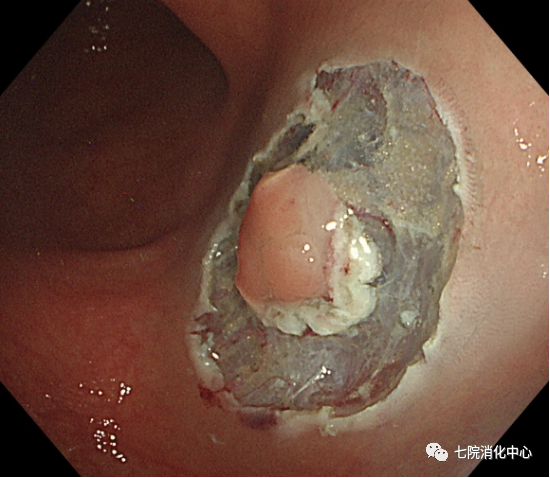

王阿姨今年65岁,前段时间总感觉肚子不舒服,大便带血,每天的排便习惯也有改变,于是来到交大附属胸科医院消化中心就诊,接诊的消化科副主任张蓉在了解其病情后,将其收治入院。入院后肠镜检查发现,其肠道内多发大小不等息肉,最大直径1.8cm.医生当即对息肉进行了切除处理,病理提示管状绒毛状腺瘤伴低级别上皮内瘤变,但庆幸的是发现较早,目前王阿姨已经康复出院,之后只需要每半年复查一次肠镜。

常用于切除无蒂息肉,通过注射缓冲液到黏膜下层的空间,使上皮与底层组织分开,使病变分离。包括整块切除和分次切除,目前黏膜下注射切除法是最常用的一种EMR切除法,其他EMR切除方法还有透明帽辅助EMR、注水法/水下法EMR等,EMR在实现大肠息肉的完整内窥镜切除术方面明显优于冷圈套器,但它需要黏膜下注射和电灼,因此不可避免出现延迟出血、息肉切除术后综合征和穿孔等并发症。

ESD相对于EMR而言,可最大限度地减少肿物的残留和复发。ESD通常应用>20mm、非颗粒样侧向发育病变。ESD相对于传统的分片黏膜切除术来说是一种复发率低、可获得更好的病理标本的技术。ESD的不足是穿孔率高、过程耗时。多项研究表明,ESD穿孔率约5%。大量研究报告了ESD的临床结果,整块切除的疗效好以及大型浅表结直肠肿瘤的长期低复发率。